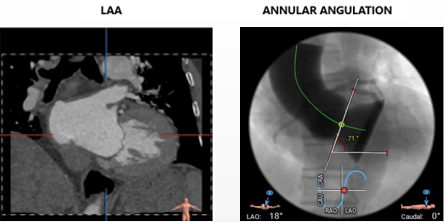

• 三叶式主动脉瓣,无钙化,瓣叶轻度增厚,结合超声为纯反流。

• 左室流出道内径大于于瓣环径,呈敞口型,瓦氏窦大小可,STJ正常,升主动脉内径可

• 主动脉瓣环与水平面夹角71度,横位心,主动脉弓角度较小,弓距长度可。

冠脉高度可,未见冗长瓣叶,左室内偏径大,横位心(71°)

• 拟置入AV29瓣膜,瓣环下0mm左右释放,跨瓣LAO 11° CAU18°(右窦中心位),释放角度 LAO 3° CAU 35(左右重合)左右,建议释放至工作位(瓣膜2/3高度)后,调整至 LAO 22° CRA11°(左冠切线位), 左右进一步确认瓣膜稳定性及瓣周漏效果后再完全释放。建议充分利用瓣膜系统部分及完全可回收功能,常规备瓣中瓣策略及外科干预策略。